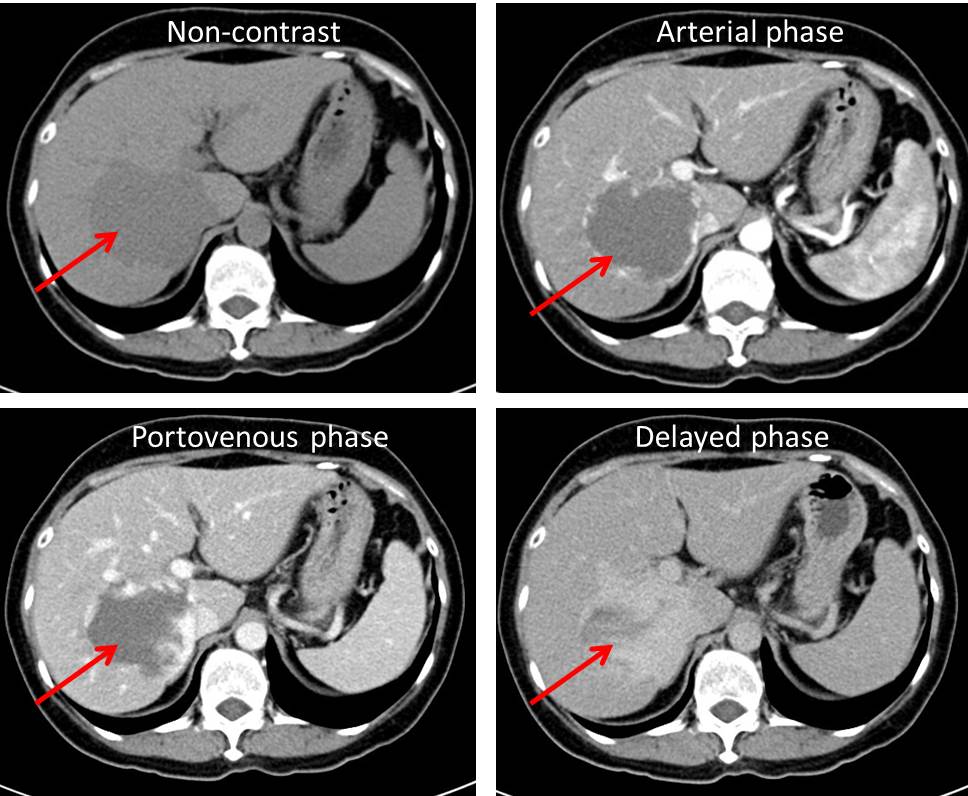

Hepatic Venous Malformation hemangioma Radiology Cases

RiT Radiology December 2010

Pneumobilia Or Portal Venous Gas Clinical Diagnostic And Therapeutic